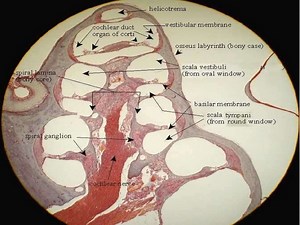

Histology - Organ of Corti

Stapes - Helicotrema

Duct - Tectorial

Labyrinth - Cochlea

- Basilar

of Ear - Organ of Corti

3D View - Organ of Corti

Canals - Sound Transduction in

Organ of Corti